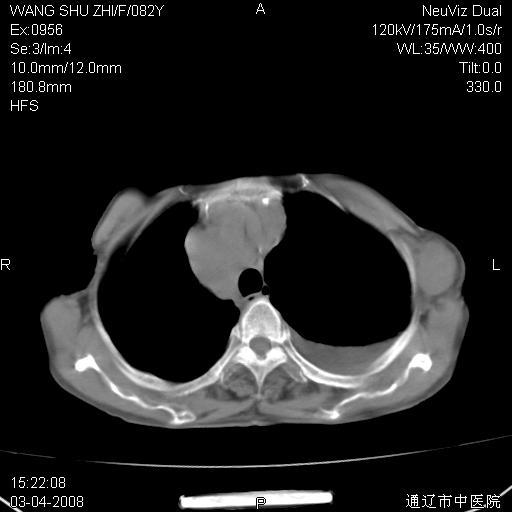

该患者为女性,82岁,既往肺心病、心衰病史。上纵隔影增宽,是否为畸形扩张的血管呢?因该患者年龄太大,又有较严重心脏病,故不适宜做增强检查。

中纵隔肿块最多见是淋巴瘤,而且以hd为多见,呈侵袭性生长,纵隔脂肪间隙消失,再加上心包和双侧胸腔积液,考虑为淋巴瘤(hd)应该说比较准确的。至于说是畸形的血管可能性小,因为畸形血管周围脂肪间隙应该存在。

纵隔淋巴结转移或淋巴瘤;双侧胸腔积液,心包积液。肺窗呢?

病史太简单,年龄太大,首先考虑转移!左侧腋窝亦见肿大淋巴结。

左侧腋窝及纵隔内见多个肿大淋巴结影,左侧少量胸腔积液,心包积液,支持淋巴瘤可能性大,不除外淋巴结转移。